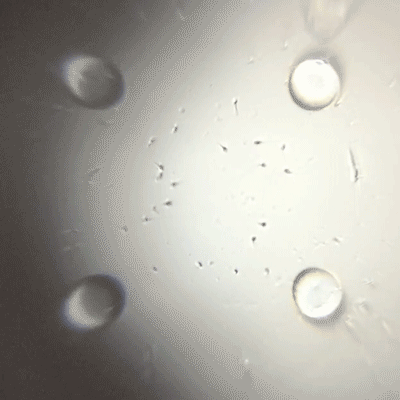

こんな動画が撮れます。レンズによって実際の300〜400倍の大きさで写しているそうです。

これは元気な精子。

でも元気じゃないとこうなります。

明らかに数が少ないですよね。